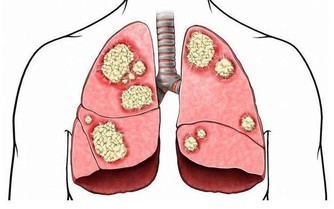

乙肝在亞非國家相當普遍,很多人也對乙肝比較重視,乙肝的傳染性雖普遍存在,

但是目前對嬰幼兒、兒童構成威脅,我國的新生兒在出生時就會安排注射乙肝疫苗,所以目前來說乙肝病毒是很難有威脅了。而對於那些少數的乙肝病毒攜帶者在治療過程中

如果不注意護理就會導致病情惡化加重,所以患者要注意乙肝惡化的前兆症狀。